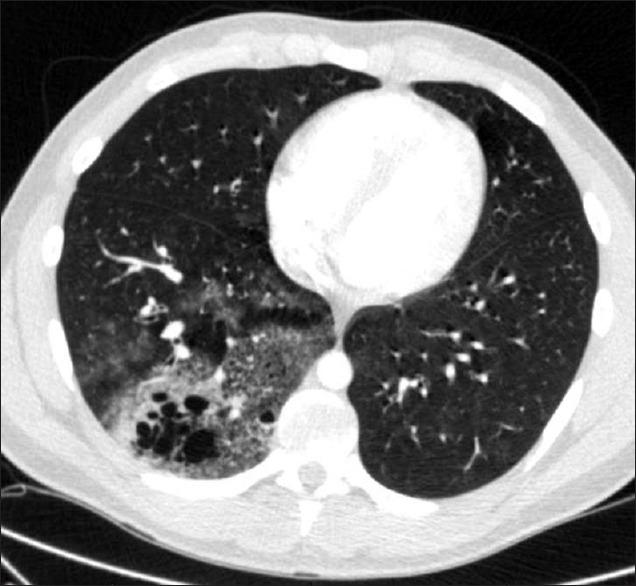

Hemoptysis from intralobar pulmonary sequestration in an adult patient.

Lung India. 2017 Nov-Dec;34(6):568-570. doi: 10.4103/0970-2113.217565.

Hemoptysis from intralobar pulmonary sequestration in an adult patient.一名成年患者因叶内型肺隔离症出现咯血。